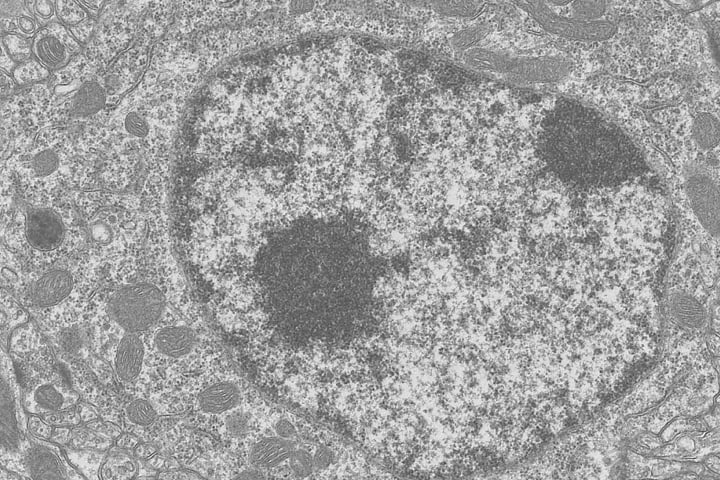

Ph.D., Pharmaceutical Sciences, The University of Tokyo (specialized in nanoscale analysis of intracellular mRNA localization and dynamics using single-molecule fluorescence microscopy).

Has also worked on the development of cell-tracking software as a postdoctoral researcher, and concurrently serves as a Research Scientist at RIKEN.